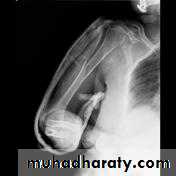

Supracondylar humeral fracture in children is one of the most common fractures seen in the pediatric orthopedic clinic setting worldwide. It's a fracture that occurs at the supracondylar area or the metaphysis of the distal humerus & accounts for 65.4% of upper extremity fractures in children .There are two types of supracondylar fractures in children according to direction of displacement of distal fragment i.e. extension type (97%) and flexion (3%).Immobilisation in an above-elbow backslab in 90 degrees elbow flexion with sling for 3 weeks. The backslab and sling should be worn under clothing (e.g. loose fitting shirt) and not through the sleeve

A gentle reduction can be achieved by an anterior push on the distal fragment as the elbow is flexed to 90 degrees

Requires urgent reduction and percutaneous pin fixation